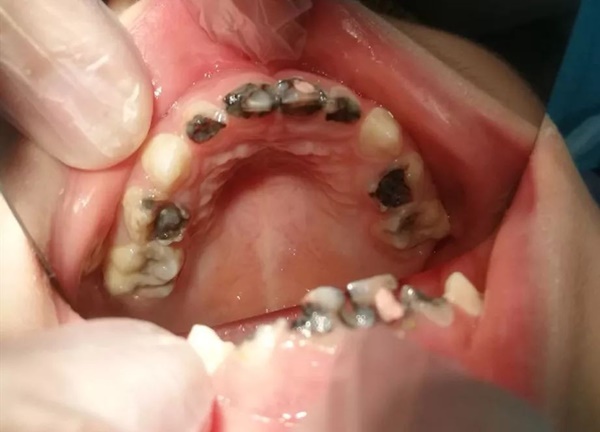

Bé 5 tuổi đã có 14 chiếc răng sâu

Mới đây, cô Trần sống tại Hải Khẩu, Trung Quốc đã dẫn con gái 5 tuổi tên là Tiểu Y đến bệnh viện khám. Khi đứa trẻ há miệng, bác sĩ vô cùng kinh ngạc khi thấy trong số 20 chiếc răng sữa thì có 14 chiếc răng đã bị sâu. Nhiều chiếc răng chỉ còn sót lại chân răng và cần phải tiến hành điều trị gấp.

Trong số 20 chiếc răng sữa thì có 14 chiếc răng đã bị sâu.